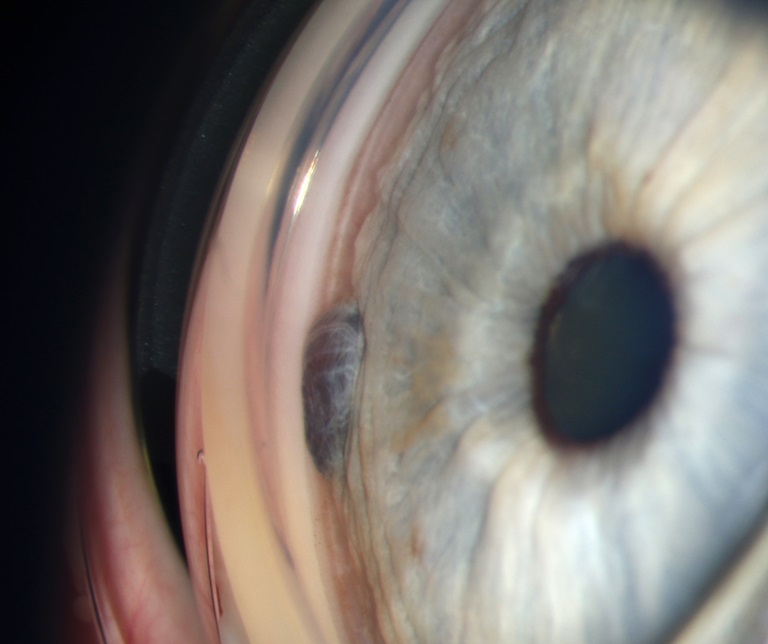

Presented by Christiaan Lopez-Miro, BAThis photograph received Honorable Mention in the category "Gonio Photography" and was displayed at the 2024 ASCRS/OPS Society Exhibit.

This photograph was presented as part of the Ophthalmic Photographers' Society Photo Exhibit at the 2024 ASCRS Annual Meeting. Browse all 2024 winning photographs using the link below.